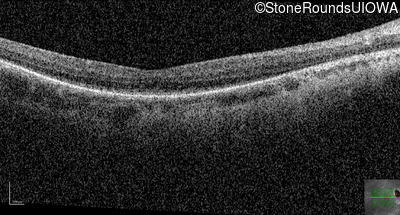

Optical Coherence Tomography - Left - 20/80 -1

Exemplar / OCT Stack

OCT Stack